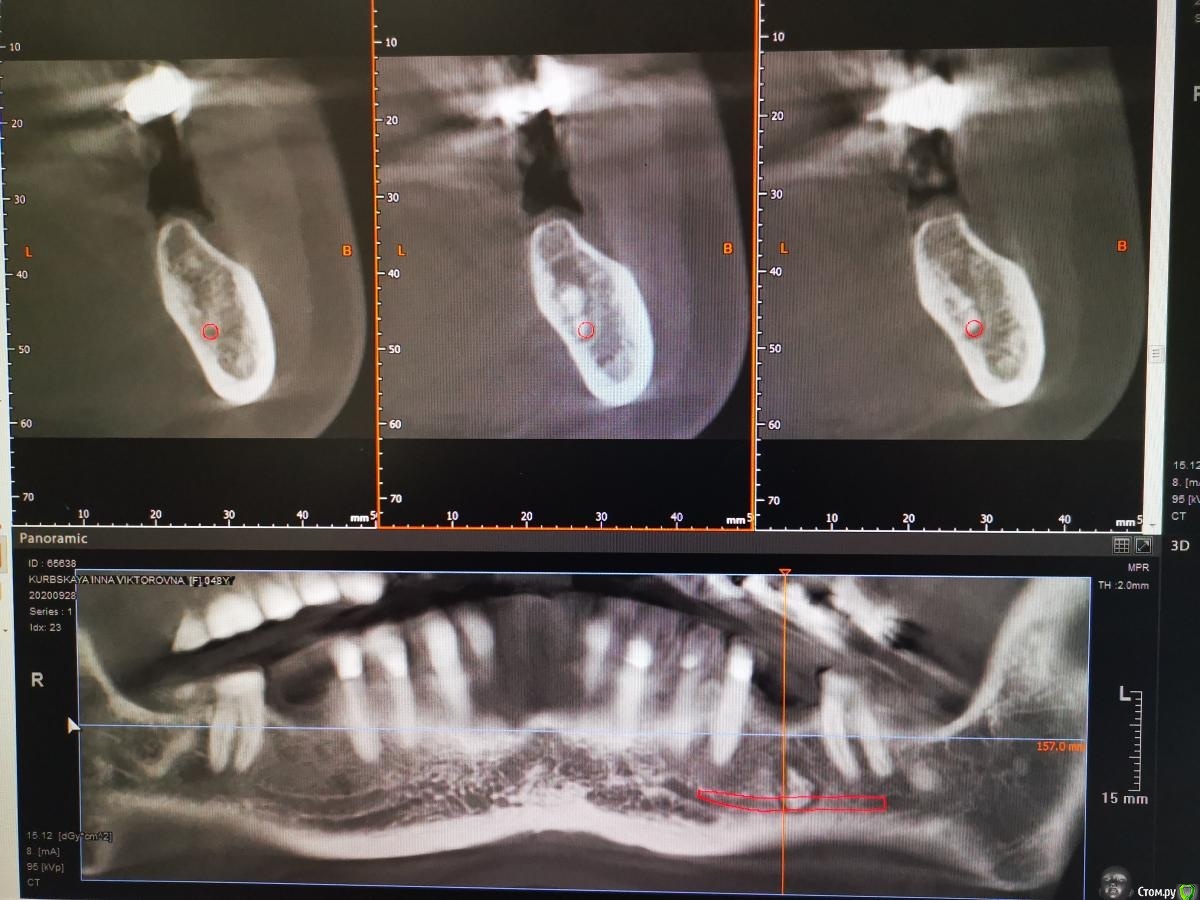

Тимур86 Опубликовано 5 ноября, 2019 Автор Поделиться Опубликовано 5 ноября, 2019 Не стоит бороться со своими желаниями... я бы удалил и гисту провёл, а потом можно и астру думаешь оно инкапсулированное? Мне кажется это типа остеомы, хотел забрать трепаном перед подготовкой ложа и на гистологию Ссылка на комментарий

red_butler Опубликовано 5 ноября, 2019 Поделиться Опубликовано 5 ноября, 2019 думаешь оно инкапсулированное? Мне кажется это типа остеомы, хотел забрать трепаном перед подготовкой ложа и на гистологиюДа, вроде капсула есть 1 Ссылка на комментарий

Тимур86 Опубликовано 5 ноября, 2019 Автор Поделиться Опубликовано 5 ноября, 2019 Ну вот на панораме вроде есть, а на срезах не сказать Ссылка на комментарий

Bier Опубликовано 5 ноября, 2019 Поделиться Опубликовано 5 ноября, 2019 а анамнез какой? может это биоосс в кисте? Ссылка на комментарий

Тимур86 Опубликовано 1 октября, 2020 Автор Поделиться Опубликовано 1 октября, 2020 Есть похожая ситуация! Но тут сложнее :глубже, и в непосредственной близости с нервом... У кого какие мысли? Ссылка на комментарий